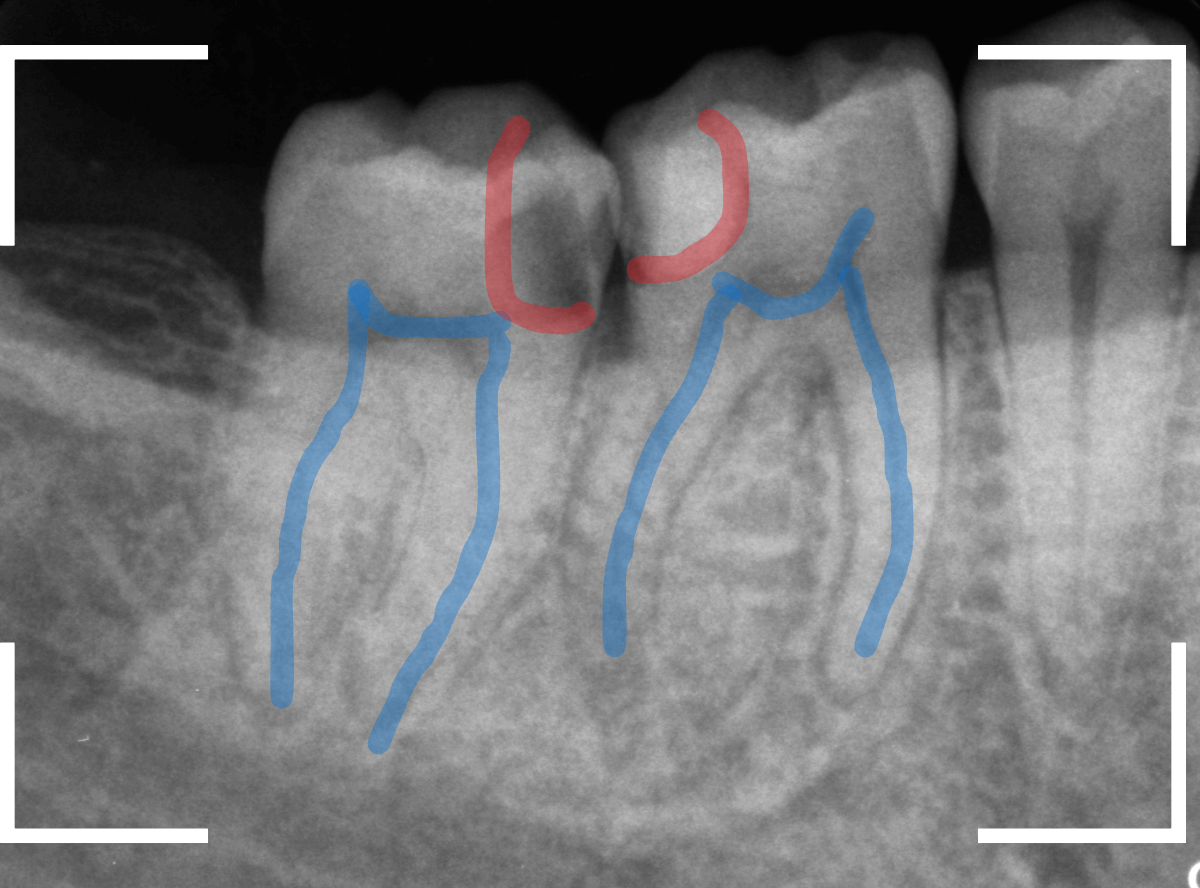

レントゲン写真で確認します。

青い線が歯の神経、赤い線が虫歯と思われる部分です。

2本とも、神経に達してしまいそうな大きな虫歯であると思われます。